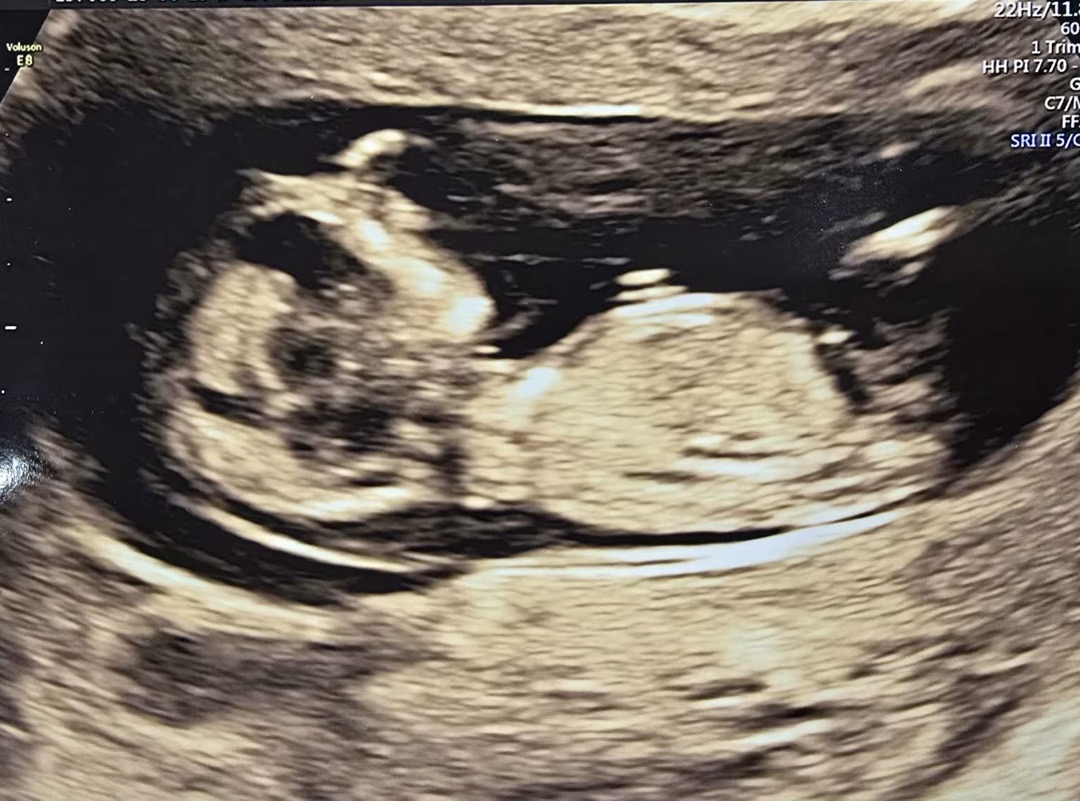

오늘 12주 2일차에 1차 기형아검사하고 왔습니다 각도법 한번 봐주세요 고수님들🙏🥹